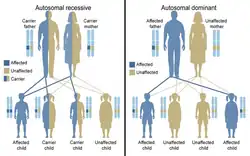

Constitutional chromosome abnormalities (present at beginning of development) arise during gametogenesis or embryogenesis, affecting a significant proportion of an organism’s cells. [23] These inherited abnormalities most commonly occur as errors in the egg or sperm, meaning the anomaly is present in every cell of the body. [1] Factors such as maternal age and environmental influences contribute to the occurrence of these genetic errors. [1] Offspring inherit two copies of each gene, one from each parent, and mutations (often caused by disease) may be passed down through generations. [24] The diseases that follow a single-gene inheritance pattern are relatively rare but affect millions of individuals. [24] This can be represented through the Mendelian inheritance patterns: [24][25]

- Autosomal dominant: Where at least one affected parent passes the mutation, and the condition appears in every generation.[24] Examples include huntington’s disease, achondroplasia, and neurofibromatosis. [24]

- Autosomal recessive: Both parents are carriers of the mutation (though it may not appear in every generation). The disorder manifests only when both copies of the inherited gene are mutated.[24] Examples include tay-Sachs disease, sickle cell anemia, and cystic fibrosis.[24]